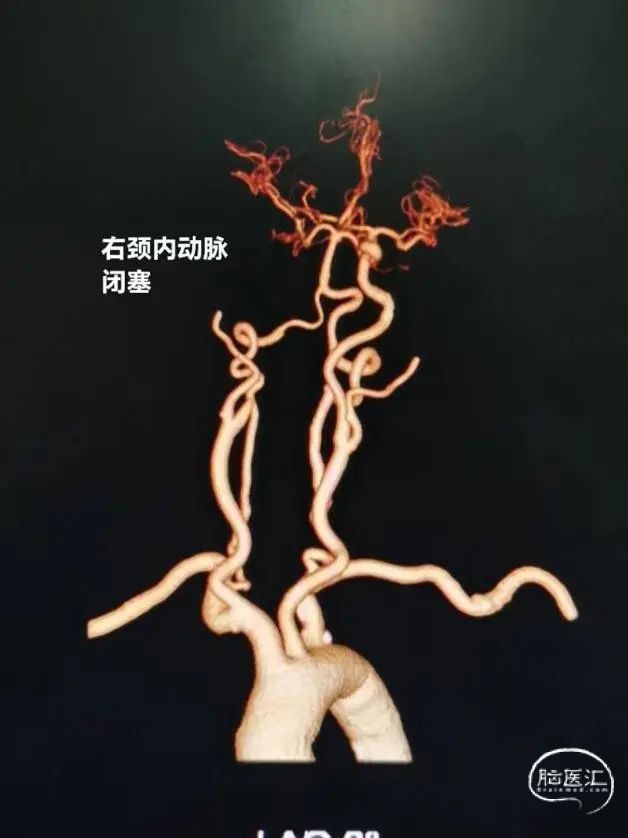

术前影像学资料

造影证实右侧颈内动脉闭塞。

患者系缺血性卒中,在静脉溶栓时间窗内,排除禁忌症,给予阿替普酶静脉66.6mg溶栓,术前NIHSS 40分,mRS 4分,并完善头颈CTA,提示右侧颈内动脉闭塞,结合心电图,考虑心源性栓塞,建议急诊血管内治疗,结合辅助检查,考虑血栓负荷量较大,首选治疗方案为支架取栓,备选导管抽栓。